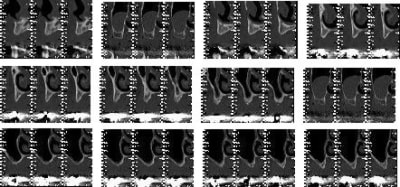

15/07/2009 à 23h52

> le pano bof...

C'est quoi ton plan de traitement ????

16/07/2009 à 01h14

>

rehabilitation max sup et inf

transvissée au max (amovo inamovible) refection 4 ccm restantes

prothese fixée à la mdble ccm sur 43

bruxisme prononcé

85 ans en pleine forme mais je fais en plusieurs fois pour ne pas trop le fatiguer.

Merci pour cette expérience partagée. Belles photos. Merci aussi d'avoir l'honnêteté de présenter un cas qui ,s'il paraît franchement parfait sur les photos de chir, l'est un poil moins sur la pano (mais c'est qu'une pano). De toute façon avec une expérience comme la tienne la gestion prothétique se fera sans doute sans trop de soucis.

pour la prothèse, je ne me fais pas de souci mais la pose sur le pano me plait tres moyennement, alors qu'en bouche ça paraissait axé comme il faut.